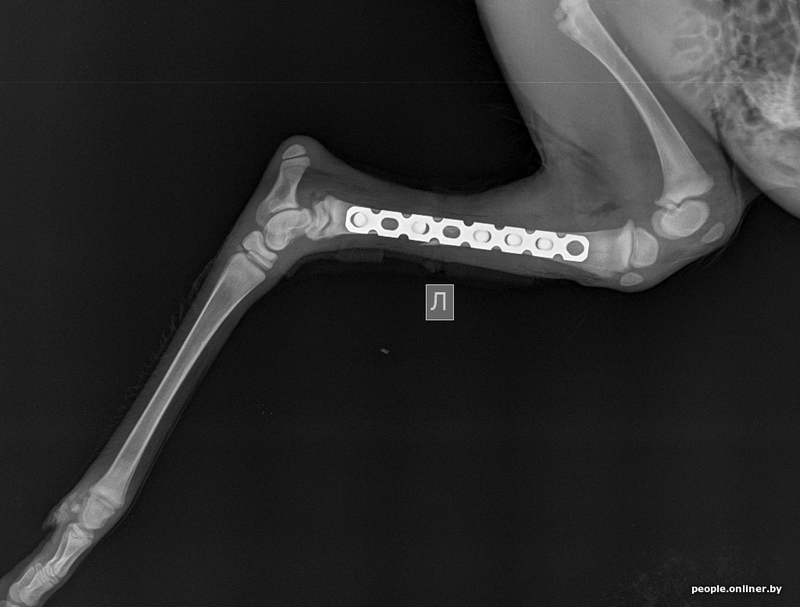

В результате операции получилась такая конструкция.